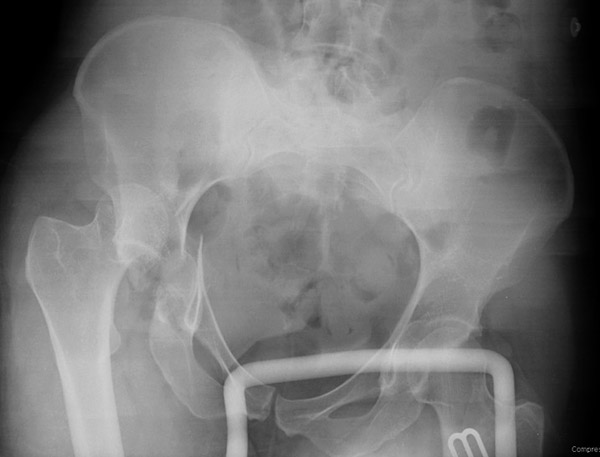

Перелом вертлужной впадины отличается от “переломов таза” не только исследованием, но также тактикой. По классификации Летурнеля расположение линии перелома характерно для поперечного перелома вертлужной впадины, но наличие шурупов в заднем крае (второй снимок) и вывих бедра подтверждают, что здесь сочетание заднего края с поперечным переломом.

Здесь пара случаев, где обычный поперечный перелом зафиксирован задним доступом и второй поперечный перелом в сочетании задней стенки, где на КТ слева в шейке обнаружен перелом без смещения, который зафиксирован профилактически.

В большинстве вывих происходит при переломах задней стенки, а без хорошей фиксации головку невозможно удержать! Про осложнения можно говорить еще, но навряд ли Вам интересно отдуваться за чужой грех. И если Вы не из WikiLeak, который сливает чужие осложнения, а ваше желание помочь искреннее, тогда надо организовать необходимые снимки и исследовании. Возможно, не все потеряно и какой-нибудь ближайщий центр протянет руки помощи....